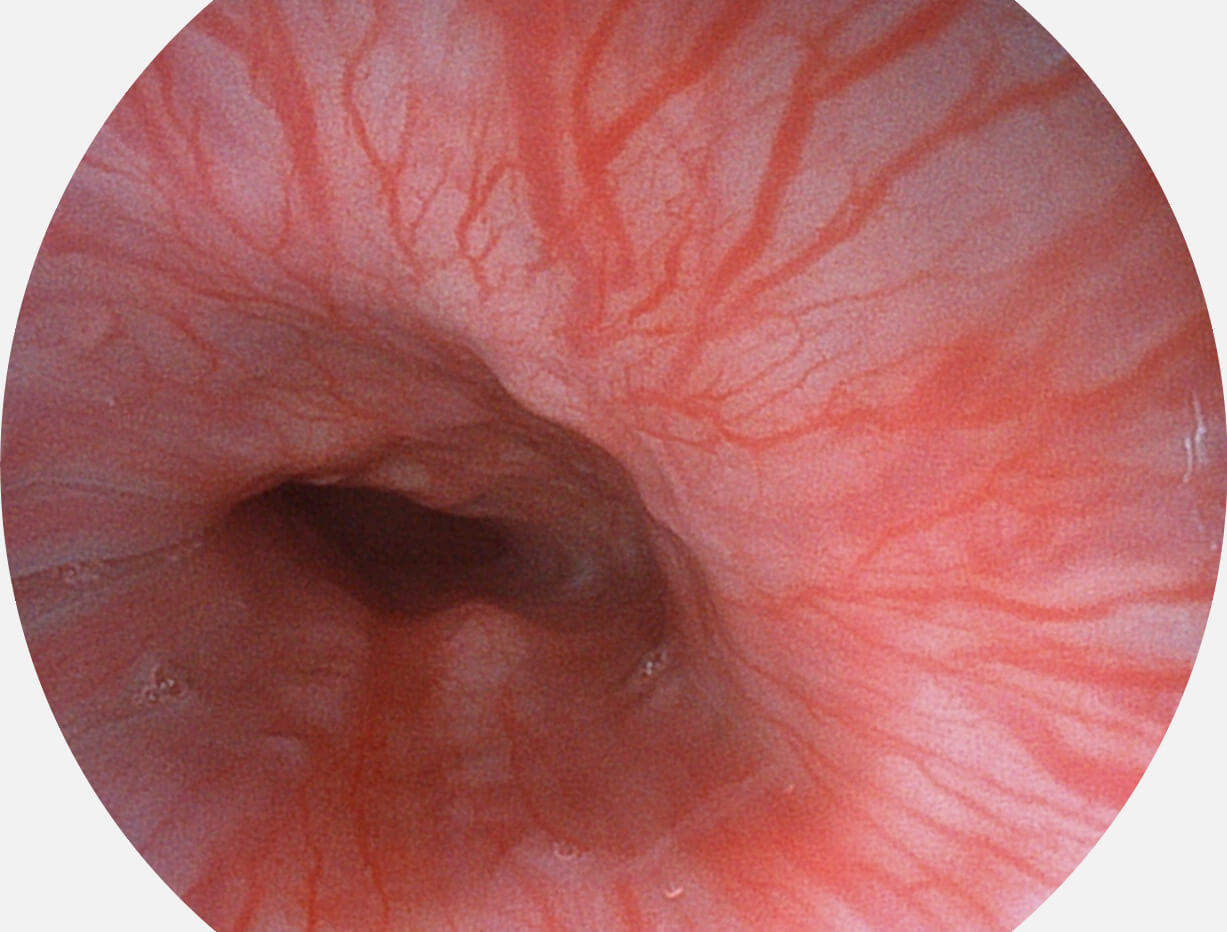

Versatile Intelligent Staining Technology, VIST

强调浅层黏膜结构的同时,保证照明亮度和提升浅层微血管与中层血管颜色对比度,病变边界更清晰。

白光图像

VIST图像